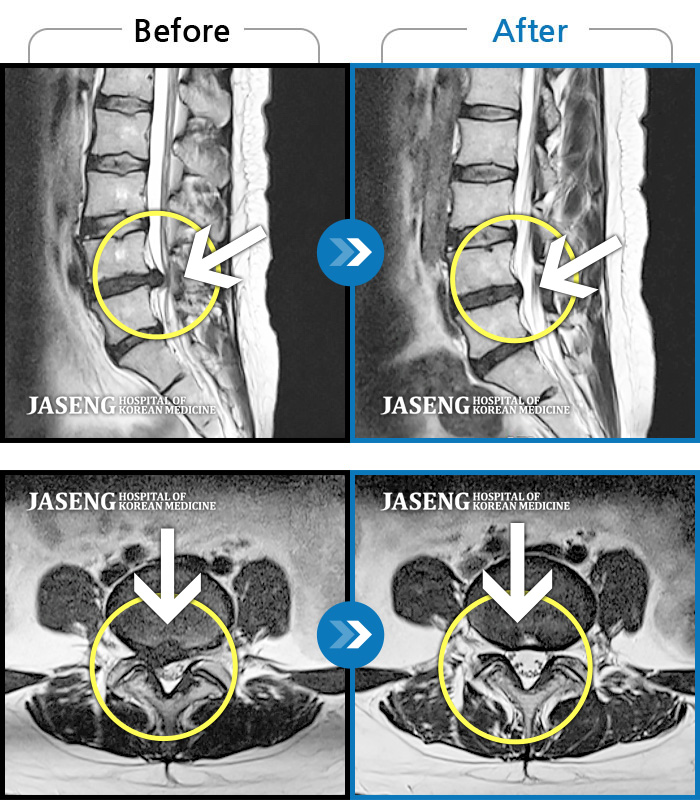

MRI 치료사례

허리와 우측골반, 우측다리 통증